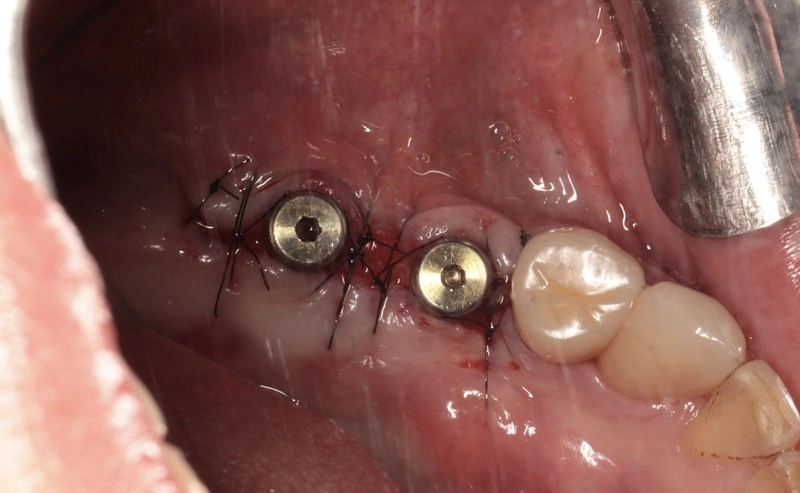

2. 3D斷層掃描再評估 與 人工牙根植入

- 精準執行: 醫師根據術前3D電腦斷層掃描的數據,精準計算骨密度、人工牙根的位置、角度與深度,將兩支人工牙根穩穩地植入重建完成的骨組織中。

- 術後呈現: 圖片中可見,植體穩定地固定在齒槽骨內,並進行了細緻的傷口縫合,等待骨整合的完成。